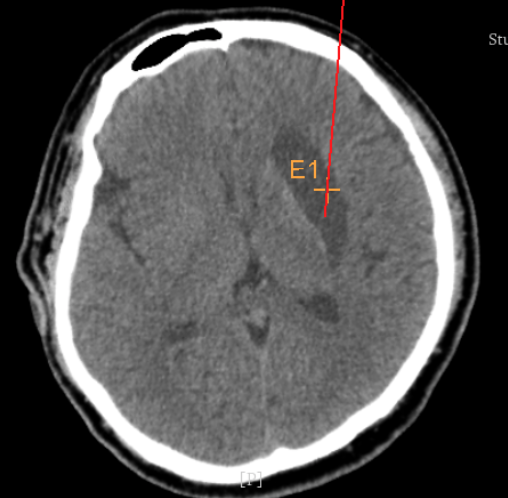

術(shù)前CT:血腫已經(jīng)液化,但仍有占位效應(yīng)

手術(shù)日當(dāng)天,醫(yī)生團(tuán)隊(duì)通過(guò)手術(shù)計(jì)劃系統(tǒng)為患者制定手術(shù)靶點(diǎn)及最安全的入顱路徑,隨后將手術(shù)規(guī)劃導(dǎo)入手術(shù)室的機(jī)器人當(dāng)中。

實(shí)際手術(shù)時(shí),機(jī)器人在幾分鐘內(nèi)就完成了空間注冊(cè),機(jī)械臂在定位儀的引導(dǎo)下自動(dòng)定位,準(zhǔn)確鎖定靶點(diǎn)。